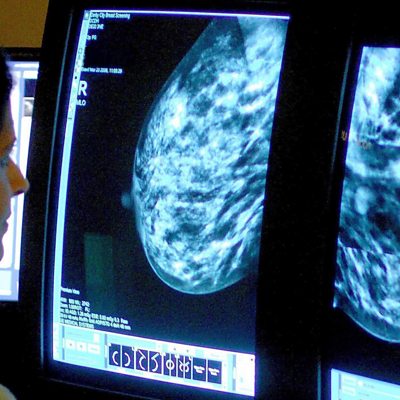

Breaking the stigma of breast cancer in the South Asian community